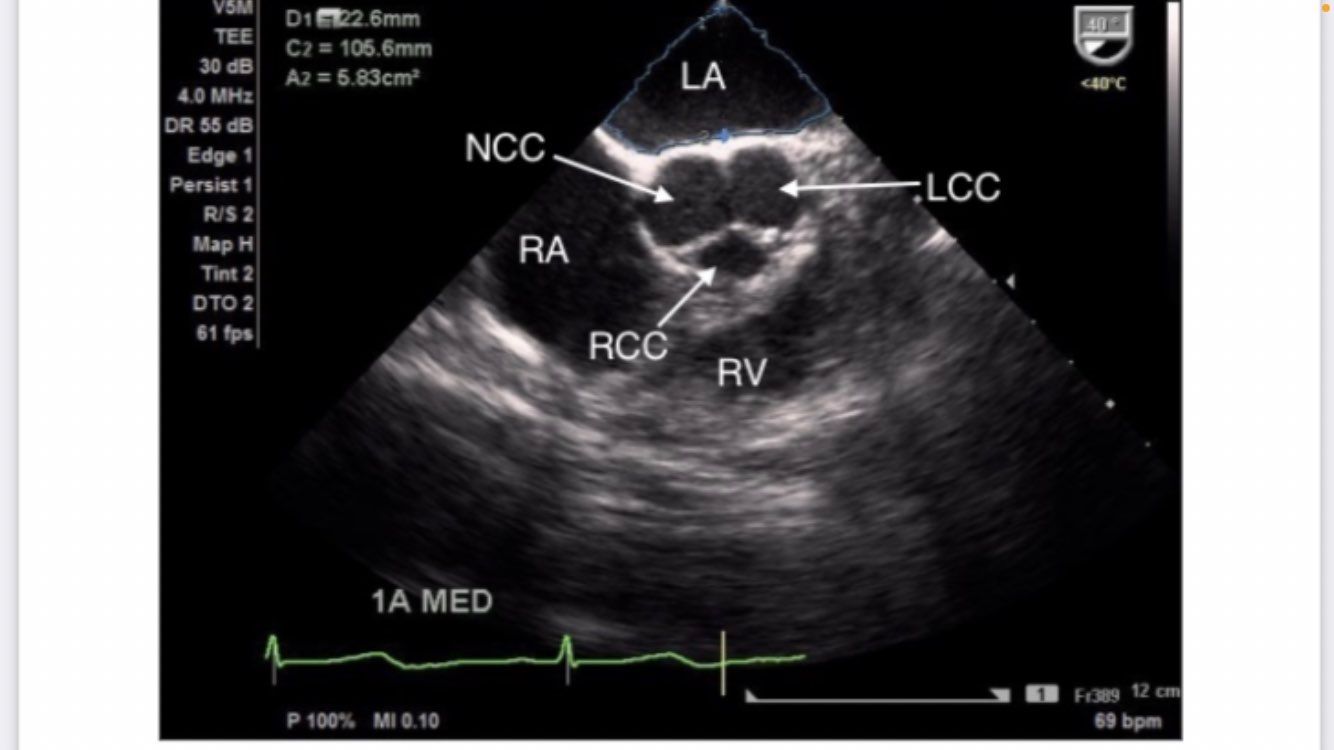

Mid-esophageal AV SAX

midesophageal aortic valve short axis